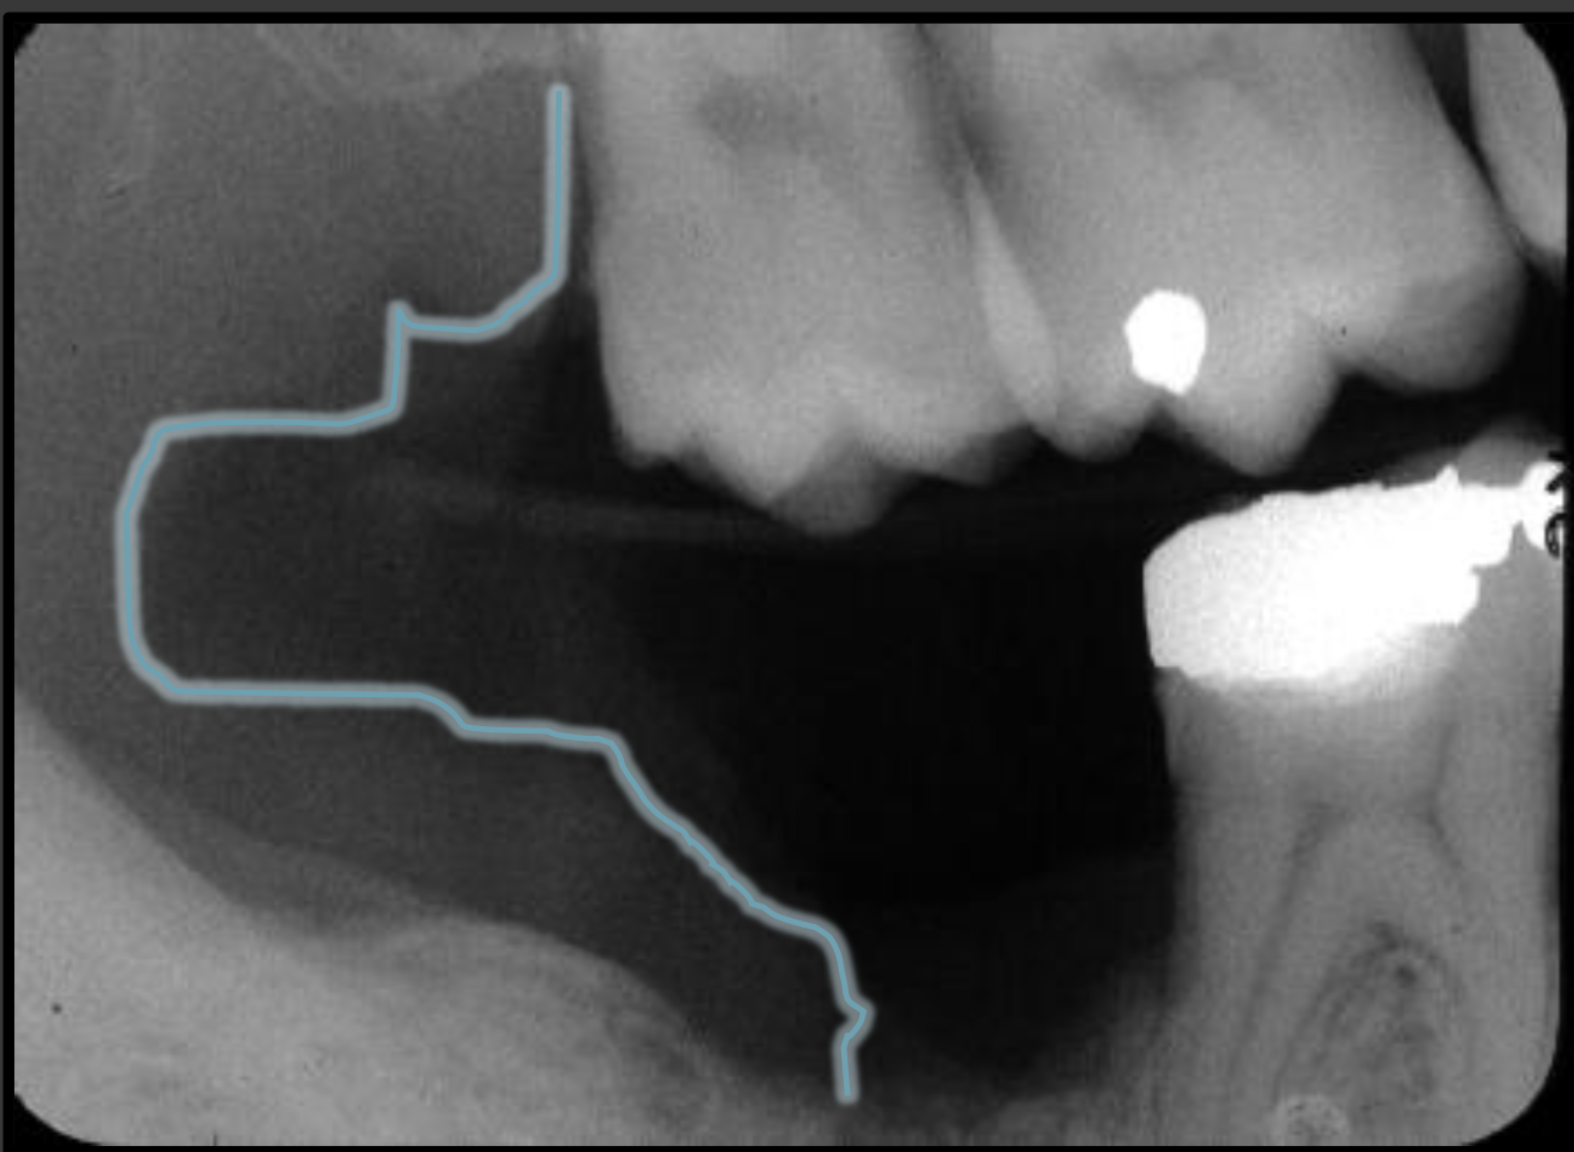

How does the mandibular canal present in a radiograph?

It is a radiolucencent band that follows the contour of the mandible that runs under the teeth.